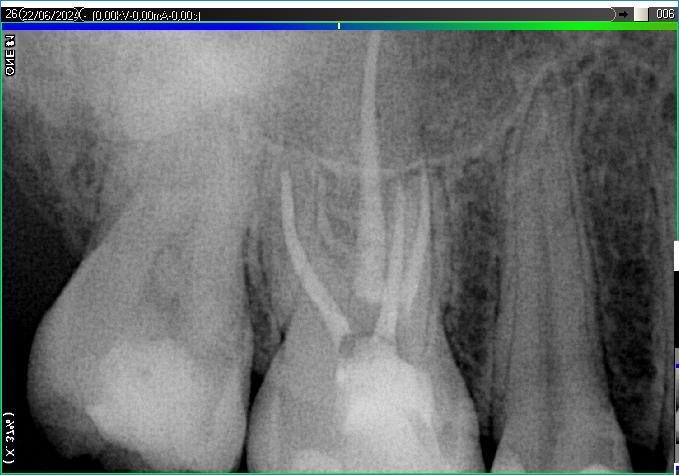

Вилучення інструменту з каналів зуба